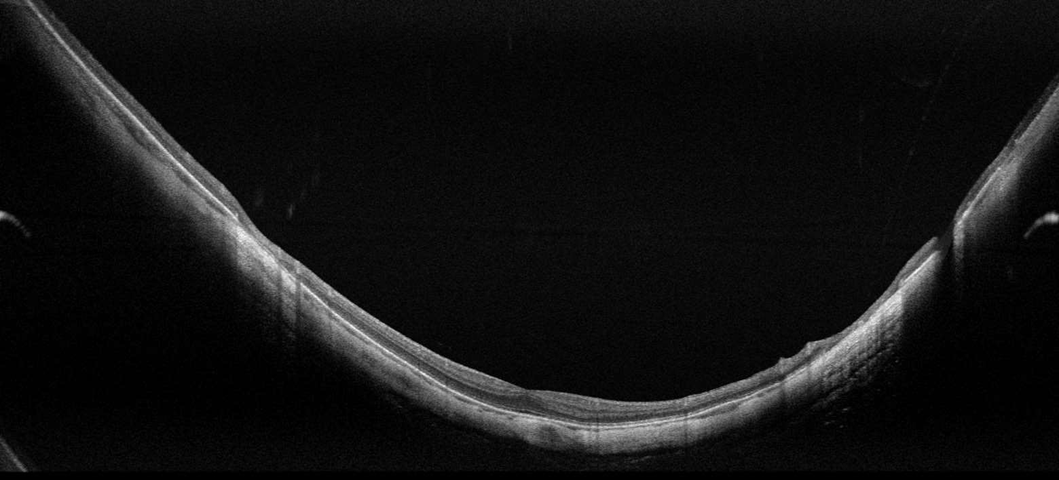

LE NOUVEAU LOGICIEL EXTENDED DEPTH ET LES CAPTURES FULL RANGE

Avec des scans présentant le nouveau logiciel Extended Depth, basé sur notre technologie Full Range, fournit des scans d'une profondeur accrue pour une observation fiable et pratique des cas difficiles. Avec des scans présentant une profondeur étendue, ce nouveau mode d'imagerie est parfait pour diagnostiquer même les patients très myopes.

- Biométrie OCT : B-OCT® est une méthode innovante d'utilisation du dispositif OCT postérieur pour mesurer la structure oculaire le long de l'axe de l'œil. Un calculateur IOL est également disponible.